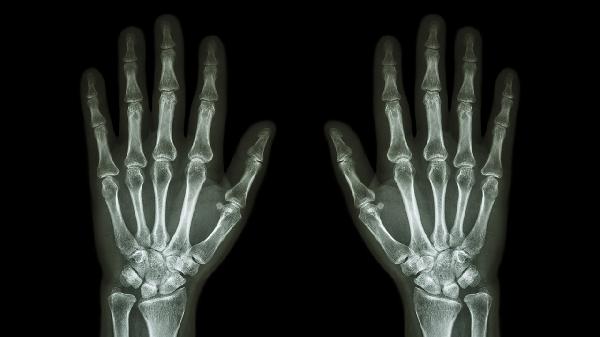

手指关节疼而且肿是什么原因

手指关节疼痛肿胀可能由骨关节炎、类风湿关节炎、痛风性关节炎、外伤或感染性关节炎等原因引起。

日常应注意关节保暖避免受凉,控制动物内脏、海鲜等高嘌呤食物摄入。适度进行手指屈伸锻炼增强关节稳定性,使用键盘时保持手腕中立位。若肿胀持续超过两周、伴随发热或关节变形,需及时到风湿免疫科就诊完善类风湿因子、尿酸及关节影像学检查。